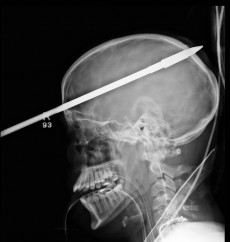

Американец, подросток, переживший травму головы